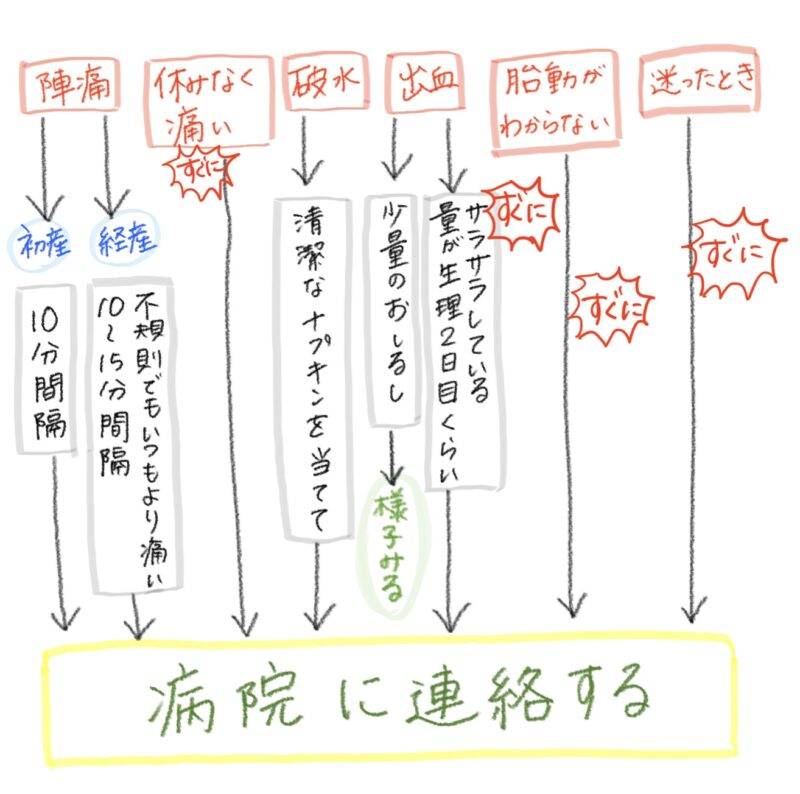

お産の電話のタイミング

陣痛

初産の場合:10分間隔になったら連絡

経産の場合:不規則であっても普段より痛みのある張りが10〜15分間隔である場合は連絡

破水

破水の場合は、シャワーには入らずに、清潔なナプキンを当てて(羊水の量が多い場合は、バスタオルを腰に巻いて)、すぐに病院に連絡をしてください。

出血

サラサラした出血、生理2日目ぐらいの量がある出血

「常位胎盤早期剥離」の疑いがあり、緊急で来ていただく必要がありますので、すぐに病院に連絡しましょう。

- 胎動がない(少ない)